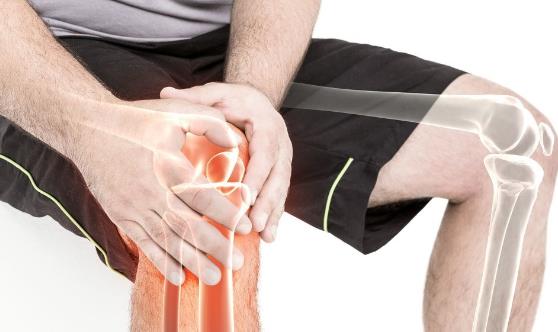

膝盖痛是现代都市人常见的症状。久坐不动、身体衰老、锻炼过度等都可能造成膝盖痛,给生活带来不便。下面跟随我们了解一下吧!减轻膝盖疼痛的有效方法减轻体重 :体重是膝盖问题的主因。你每超重一磅,你的膝盖……